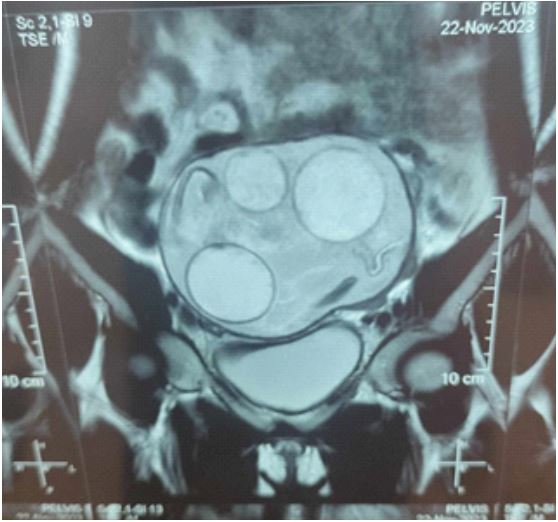

Clinical examination showed an abdominal distention; she had tenderness in the right iliac fossa. The pelvic ultrasonography revealed a 13×11 cm well-defined, heterogeneous solid-cystic cyst with no internal flow at colour doppler imaging situated in the pouch of Douglas (Figure 1) also, an accidental discovery of a 20 weeks pregnancy.

Figure 1: The MRI: showed a 13×11 cm well-circumscribed, multiloculated cystic that can be in favor of a peritoneal or ovarian hydatic cyst (Figure 2).